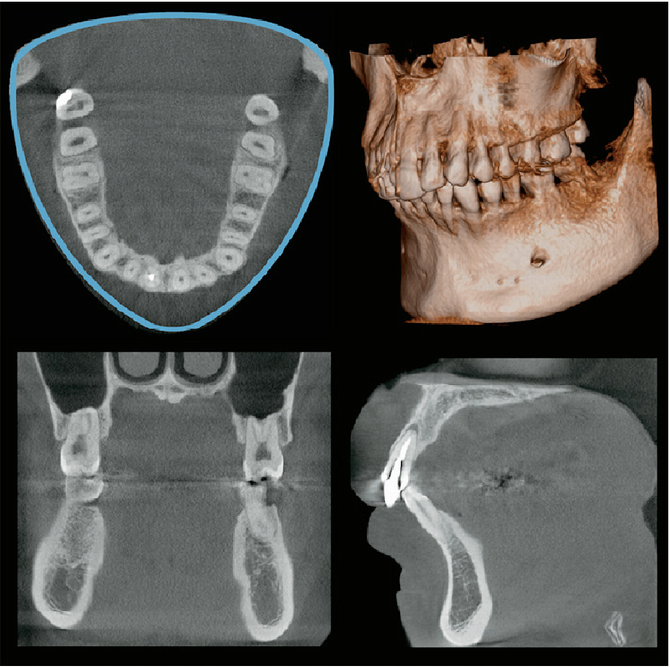

歯科撮影室:モリタ製作所 Veraview X800

パノラマ     顎関節

歯列パノラマ撮影                    顎関節撮影

セファロ2セファロ1   歯列

セファロ撮影                     歯列CT撮影